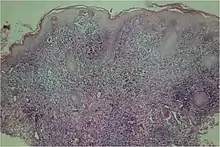

A microscopic examination of a biopsy of a yaw may show skin with clear epidermal hyperplasia (a type of skin thickening) and papillomatosis (a type of surface irregularity), often with focal spongiosis (an accumulation of fluid in specific part of the epidermis). Immune system cells, neutrophils and plasma cells, accumulate in the skin, in densities that may cause microabscesses.

Warthin–Starry or Levaditi silver stains selectively stain T. pallidum, and direct and indirect immunofluorescence and immunoperoxidase tests can detect polyclonal antibodies to T. pallidums. Histology often shows some spatial features which distinguish yaws from syphilis (syphilis is more likely to be found in the dermis, not the epidermis, and shows more endothelial cell proliferation and vascular obliteration).[2]